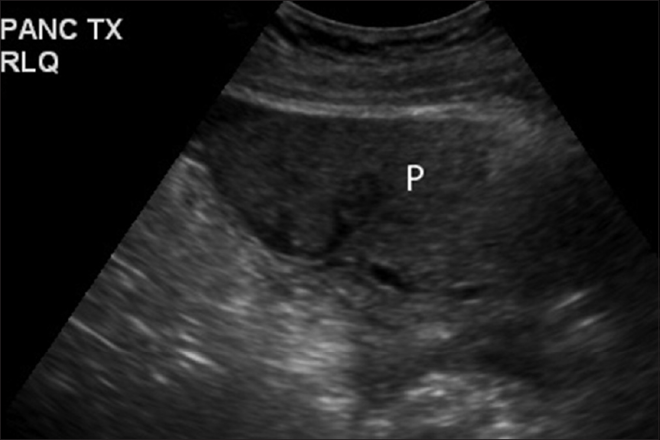

-Exploración del Páncreas:

b-Transductor localizado bajo el esternón en sentido transverso haciado angulaciones de bajo hacia arriba y se localiza el órgano por sus referencias vasculares.

c-La cola del páncreas se revisa tomando como ventana acústica al riñón izquierdo.

d-Por su localización y naturaleza solida la ecografía del páncreas tiene limitaciones. Su patología es mejor estudiada por la Tomografía axial computarizada.